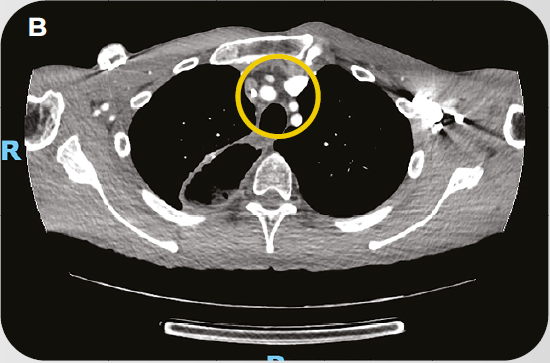

Caso Clínico: Tratamento de paciente com Câncer de Esôfago avançado com PPC>10 em 1L

O caso clínico compartilhado peo oncologista Dr. Rodrigo Guedes, constam detalhes sobre o tratamento de paciente com Câncer de Esôfago avançado com PPC>10 em primeira linha.